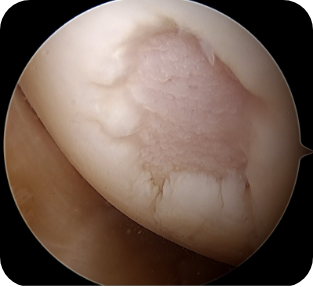

• ▲ 무릎 연골판 부분절제술 전

• ▲ 무릎 연골판 부분절제술 후

• 1) 관절경하 연골판 부분절제술

반월상 연골판 파열이 일어난 경우, 파열된 조각에 의해 관절연골이 긁혀 통증을 유발하거나 관절염이 진행될 가능성이 높을 때, 문제가 되는 연골판 부분만 절제해 주는 방법입니다. 파열된 연골판 조각이 기능을 못한다고 판단될 경우에 적용됩니다.

수술방법

관절내시경을 이용하여 무릎 안을 보면서 여러 기구를 이용하여 문제가 되는 부분만을 제거합니다.

수술장점

수술 후 특별한 운동의 제한이나 목발-보조기 등이 필요가 없습니다. 물론 동반된 다른 손상이 있어 그에 대한 치료를 할 때에는 그에 대한 재활 기간을 요합니다. 한계점으로 연골판의 결손부위가 생기는 것으로 연골판의 가장 중요한 기능인 충격 흡수, 연골의 손상예방 등에 문제가 발생합니다. 그러므로, 이미 파열된 부분이 기능을 하지 못할 때, 더 큰 손상을 일으킬 가능성이 높은 경우에만 부분제거를 고려합니다.